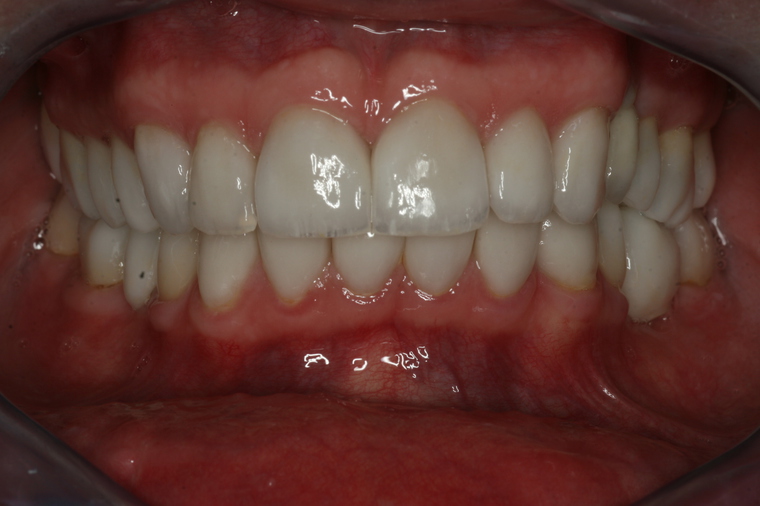

Viele Kunden die zu uns nach Salzburg kommen benötigen eine Generalsanierung der Zähne. Gründe dafür sind Zahnarztangst, Zeitmangel und schlechte Erfahrungen in der Kindheit. Unser Konzept ist genau auf diese umfangreichen Fälle abgestimmt:

Bei einer Generalsanierung müssen alle zahnmedizinischen Bereich in Betracht gezogen werden, dies beginnt bei der Aufklärung und Prophylaxe, gefolgt von Zahnfleischbehandlungen und Kariestherapie, eventuellen Zahnentfernungen, Knochenaufbauten und wird durch ästhetischen Zahnersatz abgeschlossen. Unser Recall-System hält die erreichte Zahnsanierung über lange Jahre stabil.